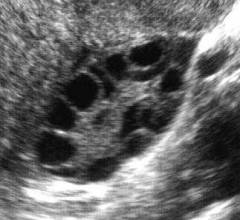

Поликистозные яичники выглядят как нормальные, но увеличены в размерах. В толще органа находится много мелких кист, которые представляют собой созревшие фолликулы, не способные прорвать оболочку яичника и высвободить яйцеклетку наружу.

- УЗИ. Одна из наиболее информативных методик, которая позволяет осмотреть и оценить внутреннюю структуру яичника, обнаружить кисты. Ультразвуковое исследование при поликистозе проводится при помощи датчика, который вводится через влагалище.